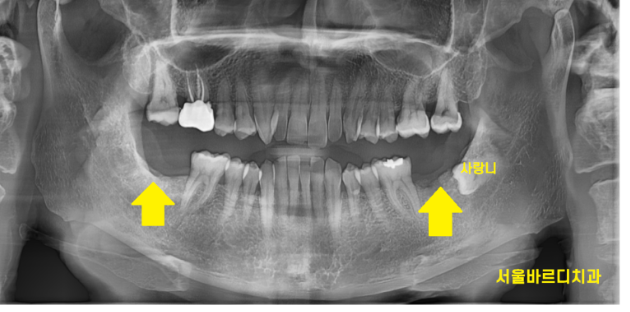

하남시청치과 처음 방문해주셨을 때

왼쪽, 오른쪽 맨 아래 끝에 어금니가

각각 1개씩 상실한 채로 오셨습니다.

231229

ct를 분석하여

모의 수술을 진행합니다.

임플란트가 들어갈 각도, 사이즈 분석해줍니다!!